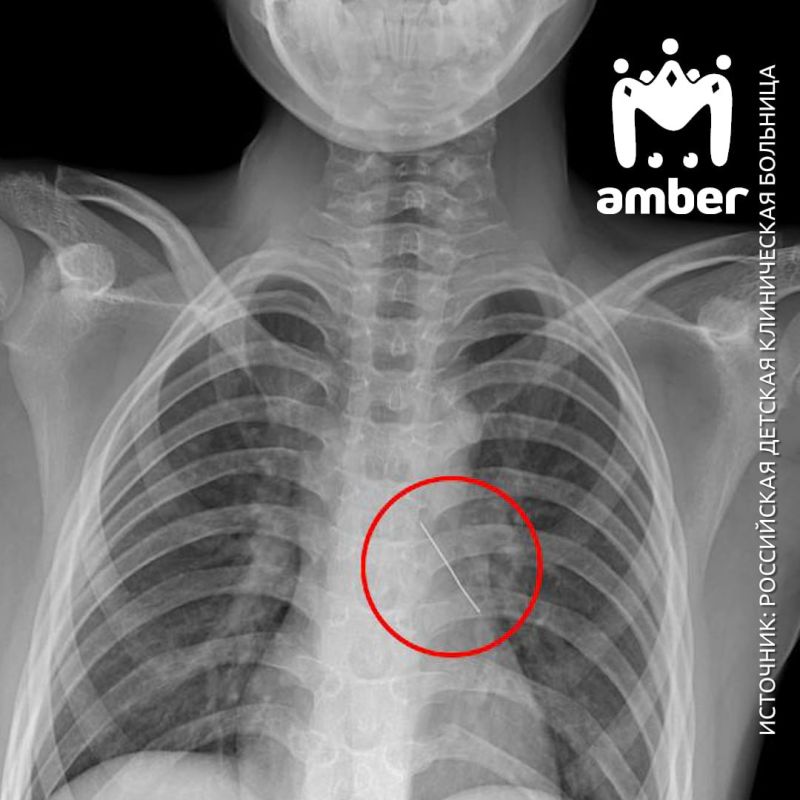

Сначала железку пытались извлечь в Калининграде — не вышло. Поэтому бортом санавиации паренька доставили в Москву. Он мог говорить только шёпотом, жаловался на сильные боли в груди. Рентген показал: булавка обосновалась в нижней доли...